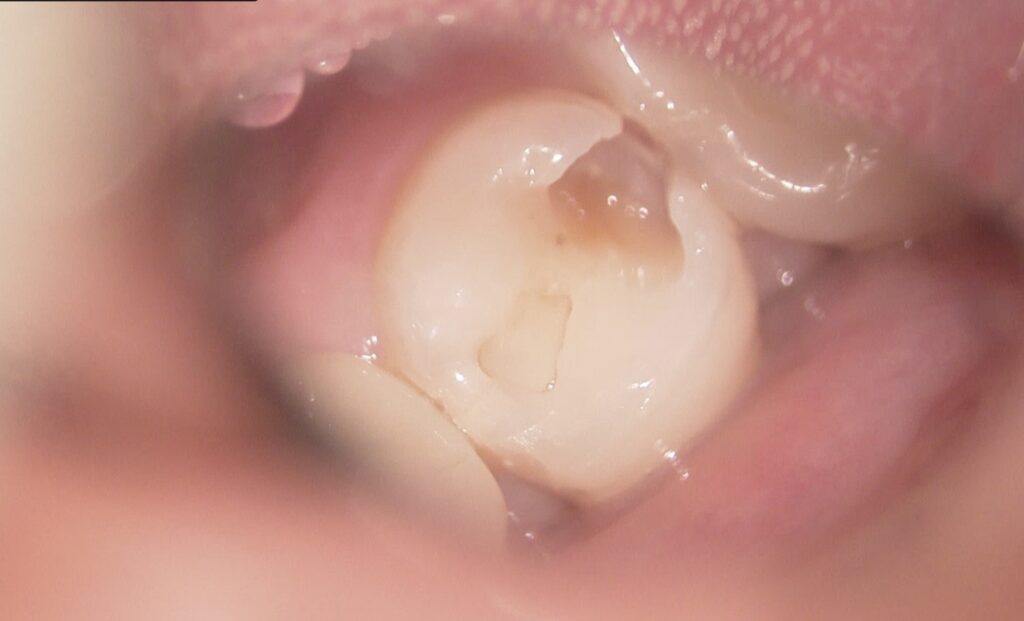

マイクロスコープは最大20倍ほど拡大して患部を確認でき、以下のようなメリットがあります:

- 虫歯の取り残しを防ぎ、再発リスクを軽減

- 歯のひびや破折を早期に発見